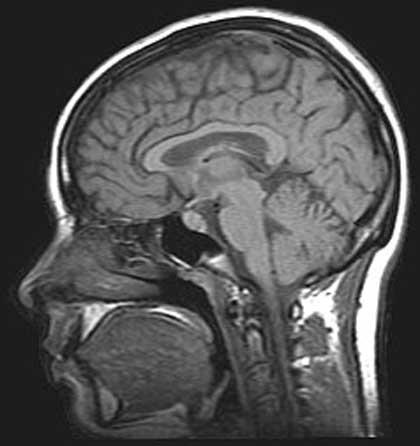

การตรวจสมองด้วยคลื่นแม่เหล็กไฟฟ้า (MRI Brain)

การตรวจคลื่นไฟฟ้าสมอง หรือ EEG นั้น จะเป็นตัวบ่งถึงสัญญาณไฟฟ้าที่ผิดปกติว่ามาจากบริเวณไหน และความถี่ของการกระจายของไฟฟ้าส่วนหนึ่งเท่านั้น แต่ EEG จะไม่สามารถบอกถึงพยาธิสภาพได้ ซึ่งในปัจจุบันทางศูนย์ฯ ได้นำ MRI Brain มาใช้ประกอบในการตรวจวินิจฉัย ประโยชน์ของ MRI Brain คือ ช่วยในการยืนยันพยาธิสภาพหลังจากตรวจ EEG แล้วว่า รอยโรคเป็นชนิดอะไร ซึ่งถ้าเราพบว่า พยาธิสภาพที่กระตุ้นให้เกิดอาการชักเกิดจากเนื้องอก หลอดเลือดผิดปกติ การรักษาก็จะไม่ใช้ยาเพียงอย่างเดียว แต่ต้องอาศัยการผ่าตัดเข้ามาประกอบด้วย